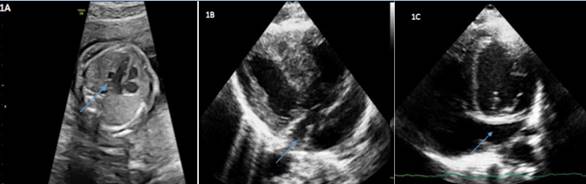

El primer caso es diagnosticado en la semana 30, tras sospecharse al visualizar un seno coronario dilatado (Figura 1A) con una imagen patológica en el corte de los tres vasos, un vaso a la izquierda del ductus en el plano tres vasos tráquea (3VT) que parecía drenar en el mismo, con un dudoso vaso a la derecha de la aorta, no claramente captante en el Doppler. No se observan otras alteraciones anatómicas en otros órganos.

Tras el nacimiento se realiza cribado de CC mediante pulsioximetría en las primeras 24 horas de vida en la planta de maternidad que supera. En la primera exploración al nacimiento no se observan rasgos dismórficos y la auscultación cardiopulmonar es normal. A las 48 horas de vida, previo al alta de la maternidad, se solicita interconsulta a cardiología infantil ante los hallazgos prenatales, realizándose ecocardiograma donde se confirma VCSIP junto con agenesia VCSD observándose también posnatalmente una dilatación del seno coronario (Figura 1B y 1C). Así mismo se observa una CIA tipo OS pequeña junto con una válvula mitral de tamaño normal, pero con apertura algo restringida por un velo posterior corto. También se realiza electrocardiograma (ECG) con resultado normal. No precisa otras pruebas complementarias en su primera valoración por cardiología infantil.